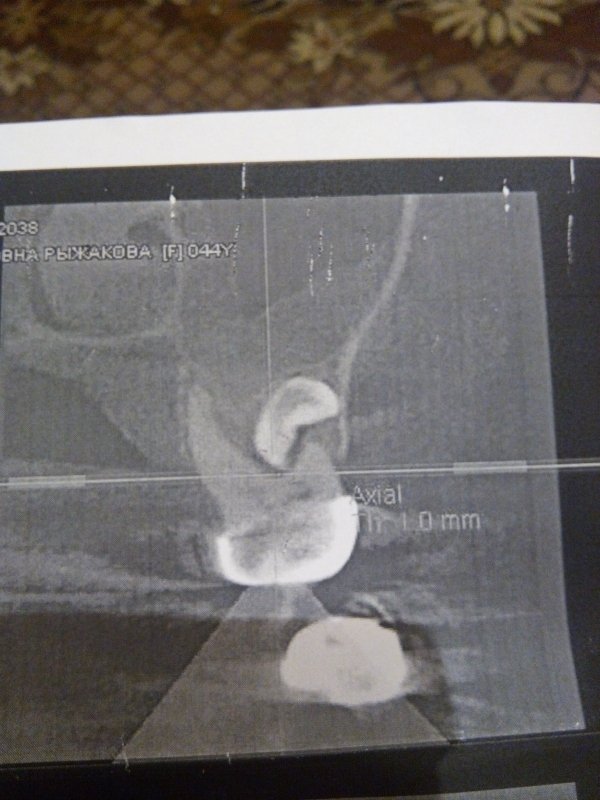

Обращалась к врачам по поводу боли при надкусывании на семерку сверху. Ответ у всех разный. Одни причину ставят - зуб мудрости под десной, который давит на семерку и его надо удалять, другие - больная семерка, а один врач сказал, что никакой восьмерки сверху у меня нет. Я в растерянности.

Я вам уже ответил, боль в седьмом зубе связана с хроническим воспалением на верхушках данного зуба. Обратитесь на очный прием в стоматологическую клинику. Мост необходимо снимать и перелечивать опорные зубы.